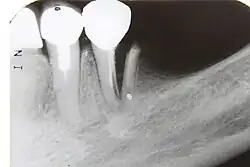

Im Verlauf einer odontogenen Infektion stirbt unbehandelt die Pulpa ab und die Keime breiten sich im System der Wurzelkanäle aus. Der Körper reagiert mit einer Entzündung des Zahnhalteapparates (Parodontitis apicalis) im Sinne einer Abwehrreaktion. Eine Parodontitis apicalis kann in einer akuten oder einer chronischen Form vorliegen. Die akute Form ist oft mit Schmerzen verbunden, sie kann unter Umständen röntgenologisch nur schwer verifiziert werden, während eine chronische Parodontitis apicalis bei einer Auflösung der Knochenstruktur im Bereich der Wurzelspitze im Röntgenbild als Aufhellung sichtbar sein kann. Im Röntgenbild erscheint die Aufhellung dunkel, da das Röntgenbild ein Negativ darstellt.

Der Ablauf einer Wurzelkanalbehandlung am Zahn 17

-

Röntgenaufnahme vor Wurzelkanalbehandlung -

Zahn eröffnet, Pulpa soll entfernt werden -

Pulpa exstirpiert -

Messaufnahme -

Drei Kanäle aufbereitet und ausgeformt -

Oft haben obere Molaren allerdings vier Kanäle -

Alle vier Kanäle abgefüllt -

Kontrollaufnahme nach Wurzelkanalbehandlung -

Deckfüllung -

Kontrollaufnahme nach 20 Monaten